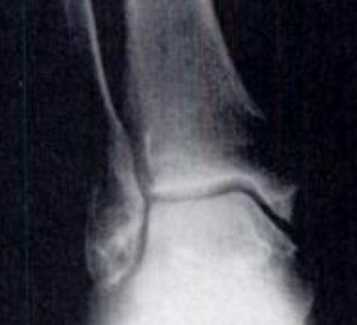

Классификация артроза голеностопного сустава.

Субхондральный склероз и начало роста остеофитов

Сужение суставной щели в медиальной области

Для диагностие выполняются рентгенограммы в прямой, боковой и косых проекциях, с нагрузкой весом тела. На рентгенограммах определяется сужение суставного пространства, субхондральный склероз, формирование кист, деформация, рост остеофитов.